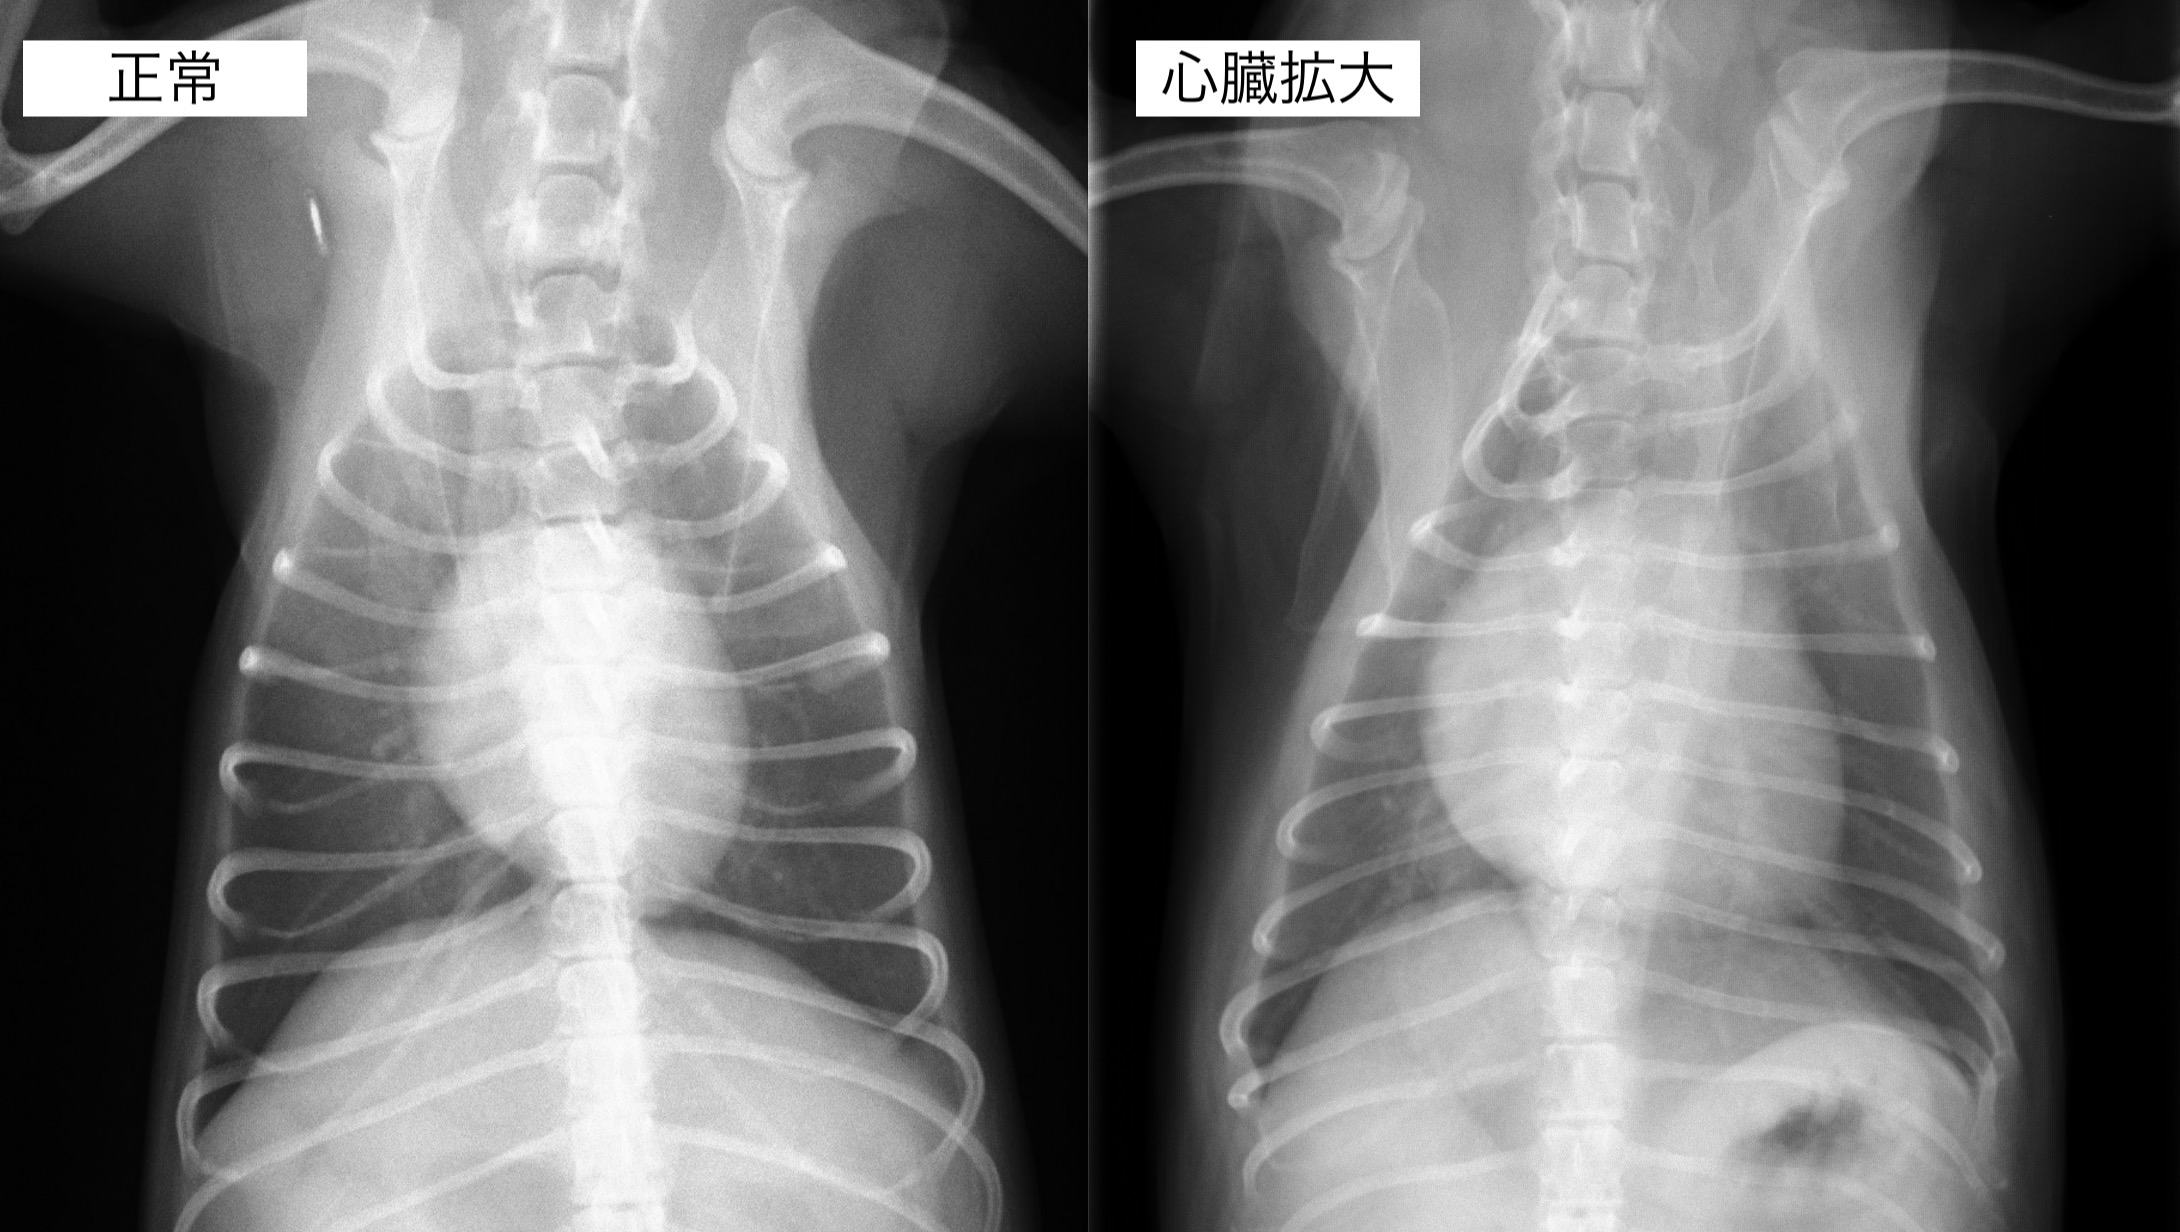

聴診検査にて心雑音が観察され、レントゲンん検査では心臓の明らかな拡大が認められました。

内服開始1ヶ月後のレントゲン検査です。

心臓の拡大はやや改善しており、咳の頻度も減っているとのことでした。